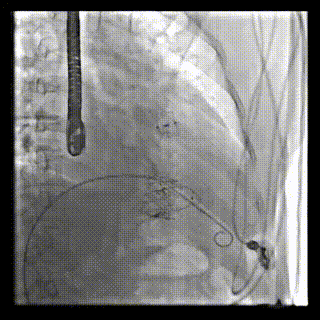

2021年12月24日,復(fù)旦大學(xué)附屬中山醫(yī)院葛均波院士團(tuán)隊成功應(yīng)用LuX-Valve Plus為一例極重度三尖瓣反流(TR)合并房顫、房缺的患者完成了經(jīng)血管三尖瓣置換術(shù),這是在前基礎(chǔ)上,本周完成的第三例經(jīng)血管三尖瓣置換手術(shù),葛均波院士、周達(dá)新教授等與心外科魏來教授、賴顥教授,心超室的潘翠珍教授、李偉教授及麻醉科的郭克芳教授共同完成了本周手術(shù),均獲得圓滿成功!患者術(shù)后超聲顯示無TR,臨床癥狀明顯改善。本周手術(shù)的成功也為LuX-Valve Plus救治性臨床研究添上了濃墨重彩的一筆。

本周三例接受LuX-Valve Plus經(jīng)血管三尖瓣置換術(shù)的患者中,第一例患者為冠狀動脈旁路移植術(shù)+Bentall+二尖瓣成形術(shù)后;第二例患者為永久起搏器植入術(shù)后,存在跨三尖瓣導(dǎo)線;第三例患者合并房顫、房缺及左心耳封堵術(shù)后。

三例患者入院后,葛均波院士團(tuán)隊周達(dá)新教授、潘文志教授、張源博士、陳莎莎博士及心超室的潘翠珍教授、李偉教授對患者的情況進(jìn)行詳細(xì)評估和討論,最終決定為三例患者選擇LuX-Valve Plus40mm、50mm和50mm型號的瓣膜進(jìn)行手術(shù)治療。手術(shù)后即刻拔除氣管插管,術(shù)后患者三尖瓣反流癥狀得到顯著改善,復(fù)查心超結(jié)果顯示人工三尖瓣瓣膜支架固定穩(wěn)定,瓣葉關(guān)閉形態(tài)未見異常,未見明顯反流。